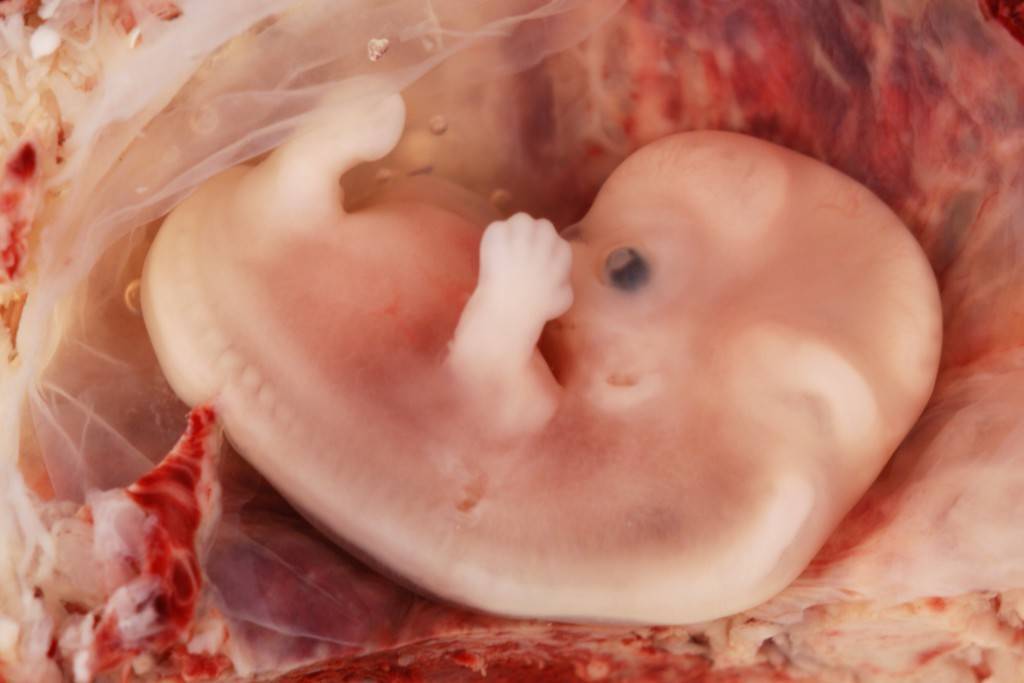

Когда виден эмбрион?

Многих интересует вопрос, на какой же неделе видно эмбрион на такой процедуре как УЗИ. Нужно сказать, что плодное яйцо можно увидеть на обследовании уже примерно с 2,5 недель беременности. На УЗИ оно выглядит темным округлым образованием, которое окружено тонкой оболочкой и имеет в диаметре до 5 мм. Сам эмбрион еще слишком мал, чтобы его рассмотреть.

5 недель. Хорошо виден плодный мешок, а также отек эндометрия

На этом сроке УЗИ используется для того, чтобы подтвердить саму беременность. Через пару недель плодное яйцо становится больше и гораздо заметнее. К четырем неделям беременности оно равняется в диаметре примерно 2 см, увеличивается матка. На каком же сроке видно сам эмбрион на экране аппарата УЗИ? Разглядеть его можно только с пятой недели беременности: видно будет продолговатый объект, крепящийся будущей пуповиной к стенке плодного яйца.